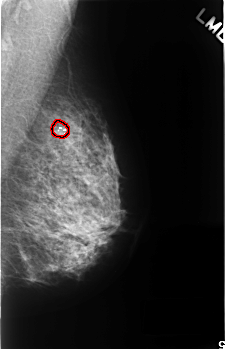

FILE: C_0341_1.RIGHT_MLO.OVERLAY

TOTAL_ABNORMALITIES 1

ABNORMALITY 1

LESION_TYPE CALCIFICATION TYPE FINE_LINEAR_BRANCHING DISTRIBUTION SEGMENTAL

ASSESSMENT 5

SUBTLETY 5

PATHOLOGY MALIGNANT

TOTAL_OUTLINES 1

BOUNDARY